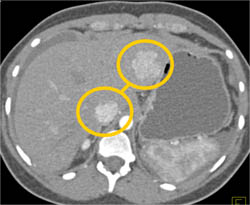

Diagnosis

Focal Nodular Hyperplasia (FNH)